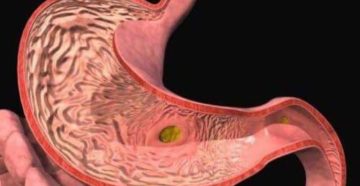

Строение и функции желудка Пациент жалуется врачу на боли в желудке. А спросишь подробнее, так…